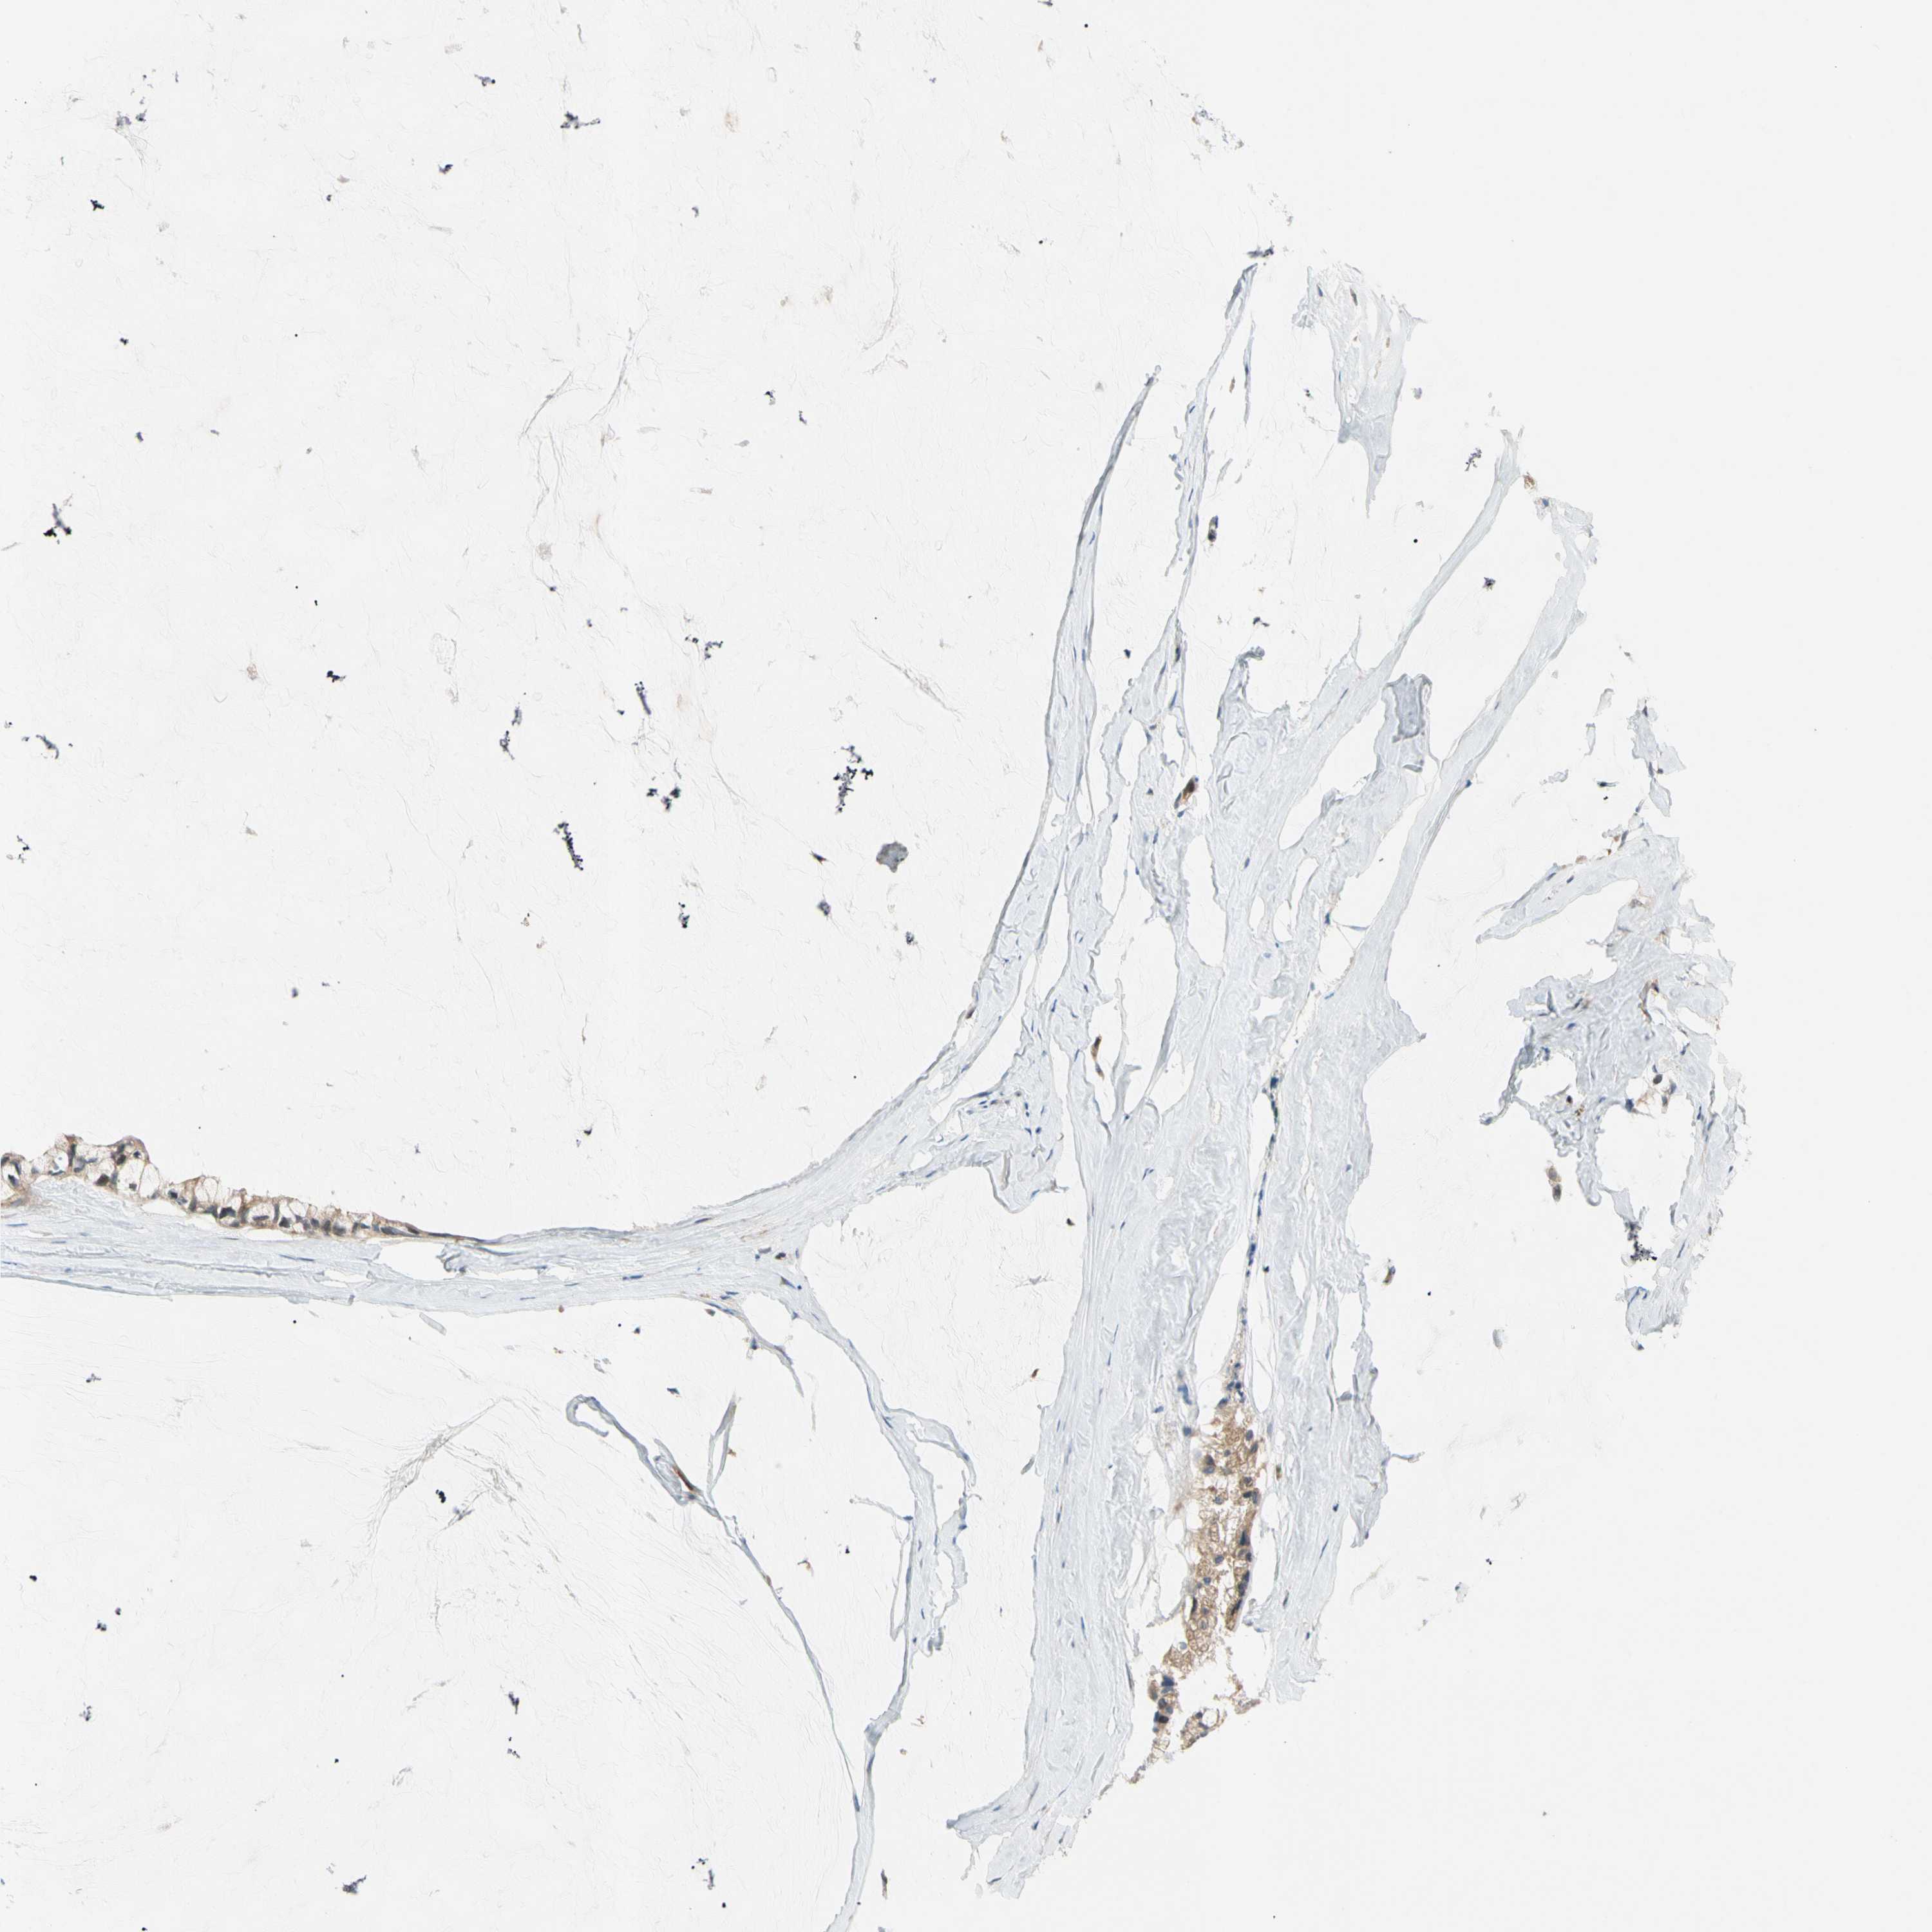

OVARIAN CANCER - Protein expressioni

A mouse-over function shows sample information and annotation data. Click on an image to view it in a full screen mode. Samples can be filtered based on level of antibody staining by selecting one or several of the following categories: high, medium, low and not detected. The assay and annotation is described here.

Note that samples used for immunohistochemistry by the Human Protein Atlas do not correspond to samples in the TCGA dataset.

Antibody stainingi

Antibody staining in the annotated cell types in the current human tissue is reported as not detected, low, medium, or high, based on conventional immunohistochemistry profiling in selected tissues. This score is based on the combination of the staining intensity and fraction of stained cells.

Each image is clickable and will lead to virtual microscopy that enables deeper exploration of all samples and also displays staining intensity scores, fraction scores and subcellular localization as well as patient and tissue information for each sample.

Antibody HPA008812

Staining

High

Medium

Low

Not detected

Intensity

Strong

Moderate

Weak

Negative

Quantity

>75%

75%-25%

<25%

None

Location

Nuclear

Cytoplasmic/membranous

Cytoplasmic/membranous,nuclear

Cystadenocarcinoma, serous, NOS

Carcinoma, endometroid

Cystadenocarcinoma, mucinous, NOS

Carcinoma, NOS